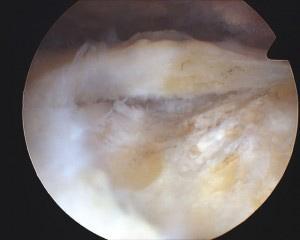

Tear debrided

Anchor placed in bone